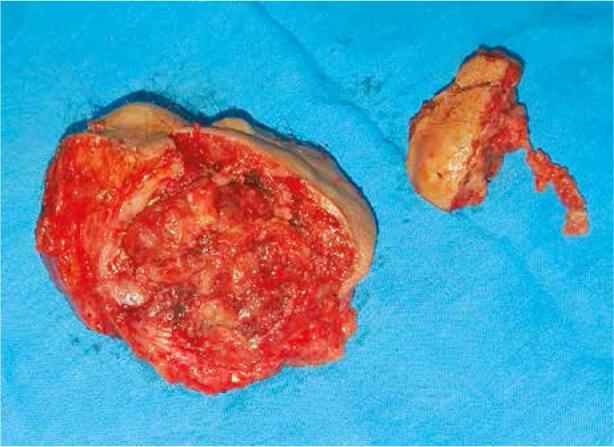

We report a case of a 73-year old patient in whom the disease was manifested by pain syndrome and rapidly growing mass with irregular margins in the symphysis area and satellite nodules. She underwent extensive local excision followed by radiation therapy.

我们报告一例73岁患者,该疾病表现为疼痛综合征,耻骨联合区域有边缘不规则且迅速生长的肿块及卫星结节。她接受了广泛局部切除,随后进行放射治疗。